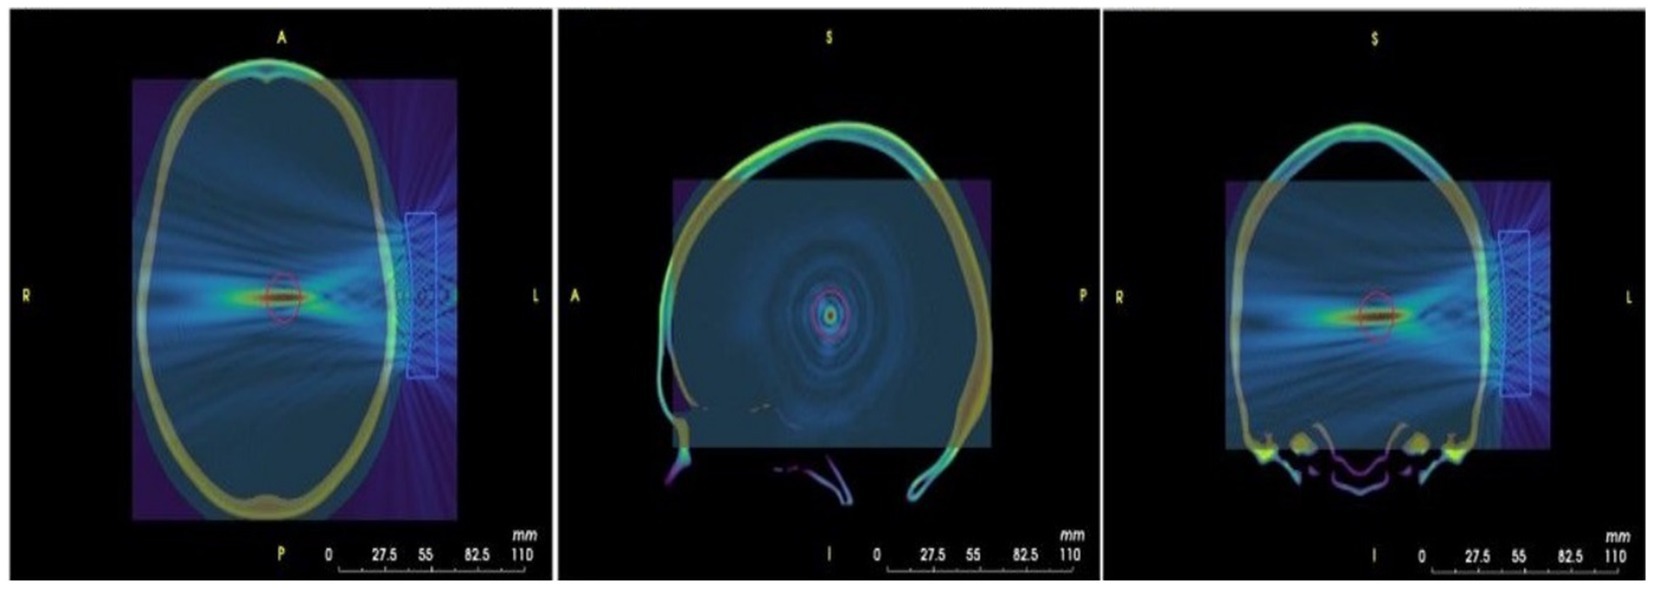

Figure 6

Pressure maps derived from ultrasound modeling superimposed on the MRI image of the MNI template, which was obtained from k-Plan.

2.3.4 Simulations (k-Plan)

We will utilize k-Plan software to conduct our simulations, using a transducer model configured according to the physical properties of the NeuroFUS transducer and the phase settings specified for the TPO unit. Given the deep subcortical location of the left and right thalamus, we will simulate the ultrasound beam with a focal depth tailored to the target distance determined by Brainsight, which individually reflects the focal depth required for each participant’s anatomical structure. Transcranial simulations targeting the left or right thalamus will be performed for each participant. All patients will have undergone a cranial CT scan during their hospital stay, which will be used for default CT calibration. We will use 3D Slicer to co-register the head CT data with the participant’s T1-weighted MRI to ensure precise anatomical alignment. Following the simulation, relevant reports and results will be generated. Based on these outcomes, we will identify the optimal stimulus location. Subsequently, Brainsight software will be used to guide and implement the stimulation procedure in accordance with the simulation results. (Illustrative images are provided in Figure 6). The simulated images displayed in Figure 6 were generated using standardized neuroimaging templates. The MR template employed in k-Plan corresponds to the ICBM 1522009c Nonlinear Symmetric template (1 × 1 × 1 mm resolution; filename: mni_icbm152_t1_tal_nlin_sym_09c.nii), as described by Fonov et al. (37). The CT template implementation follows the methodology outlined by Rorden et al. (38). For additional technical details regarding these planning images, please refer to the official k-Plan documentation available at.1